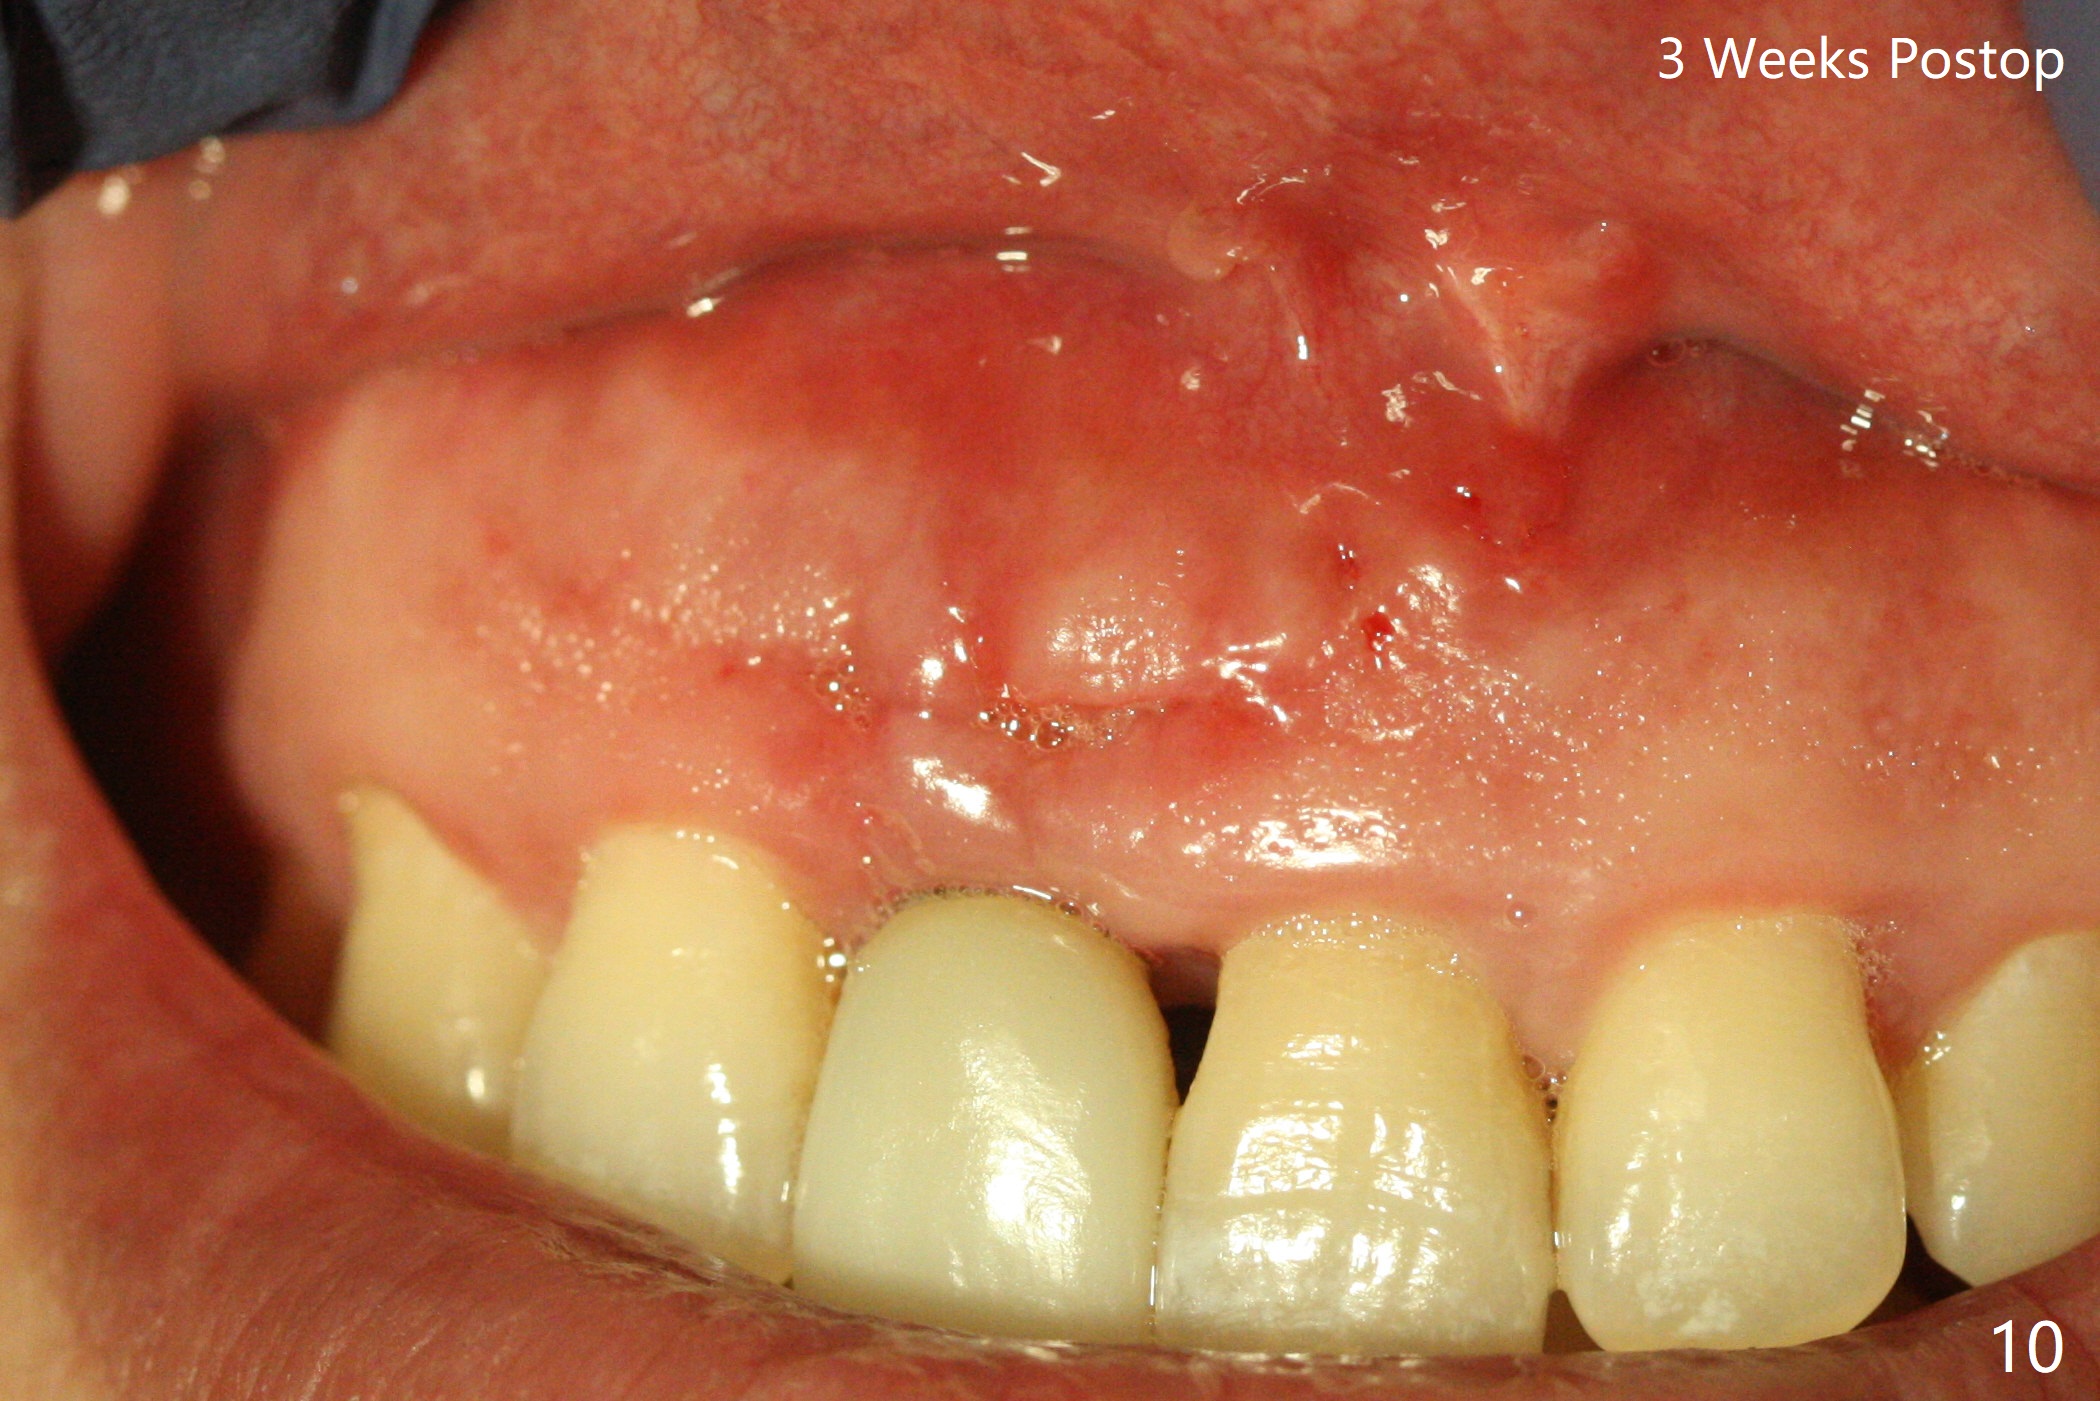

The patient returns because of purulent exudate from the buccal fistula (Fig.1 *) 1 year 9 months postop (1 year 3 months post cementation). Preop CT shows buccal thread exposure (Fig.2 arrowheads). To prevent postop gingival recession, a semilunar incision is made between the fistula and the gingival margin (Fig.3). After removal of granulation tissue (Fig.4), allograft in sticky bone form is packed (Fig.5). Following placement of PRF membrane and 6-month collagen membrane, the wound is closed (Fig.6). Since the implant (Fig.7 I) thread exposure is within bone (B) boundary (Fig.8 red dashed line), bone graft with PRF should be able to take care of periimplantitis (A: abutment). To prevent periimplantitis in similar situation, the immediate implant should be placed deep (not necessarily long, 18 mm) and narrower (3.5 mm instead of 3.8 mm). The defective buccal plate should be repaired with sticky bone and collagen membrane with incision if necessary. The wound does not dehisce 1 week postop (Fig.9) or 3 weeks postop (Fig.10, immediately post suture removal). Although bone graft seems to stay in place 6 months postop (Fig.11,12), the patient complains of bone graft expulsion sometimes. The buccal gingiva has deficiency (Fig.13). To fix it, make a remote incision (Fig.14 black line) and dissect before gingiva graft (Fig.15 dashed line). After removal of crown/abutment, the sinus track and implant surface are treated with Waterlase. A shorter cuff abutment is placed (4.5x5(4 to 3) mm) with a new provisional. The patient feels better with reduced sinus track 2 weeks postop (Fig.16).